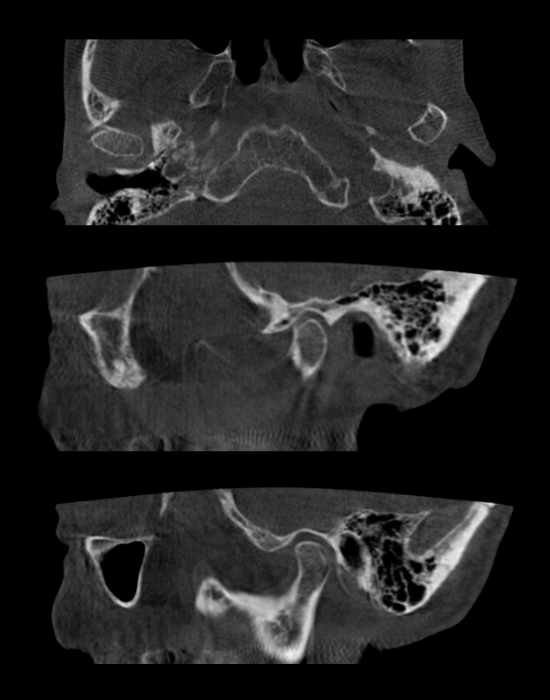

3д діагностика скронево-нижньощелепних суглобів

Блок 1. 3д діагностика скронево-нижньощелепних суглобів

✅ Нормальна анатомія СНЩС на КПКТ

✅ Розміри голівки СНЩС, рентгенологічна суглобова щілина

✅ Диференційна діагностика дегенеративних змін СНЩС. Клінічні приклади

✅ Дислокації голівок СНЩС. Клінічні приклади.